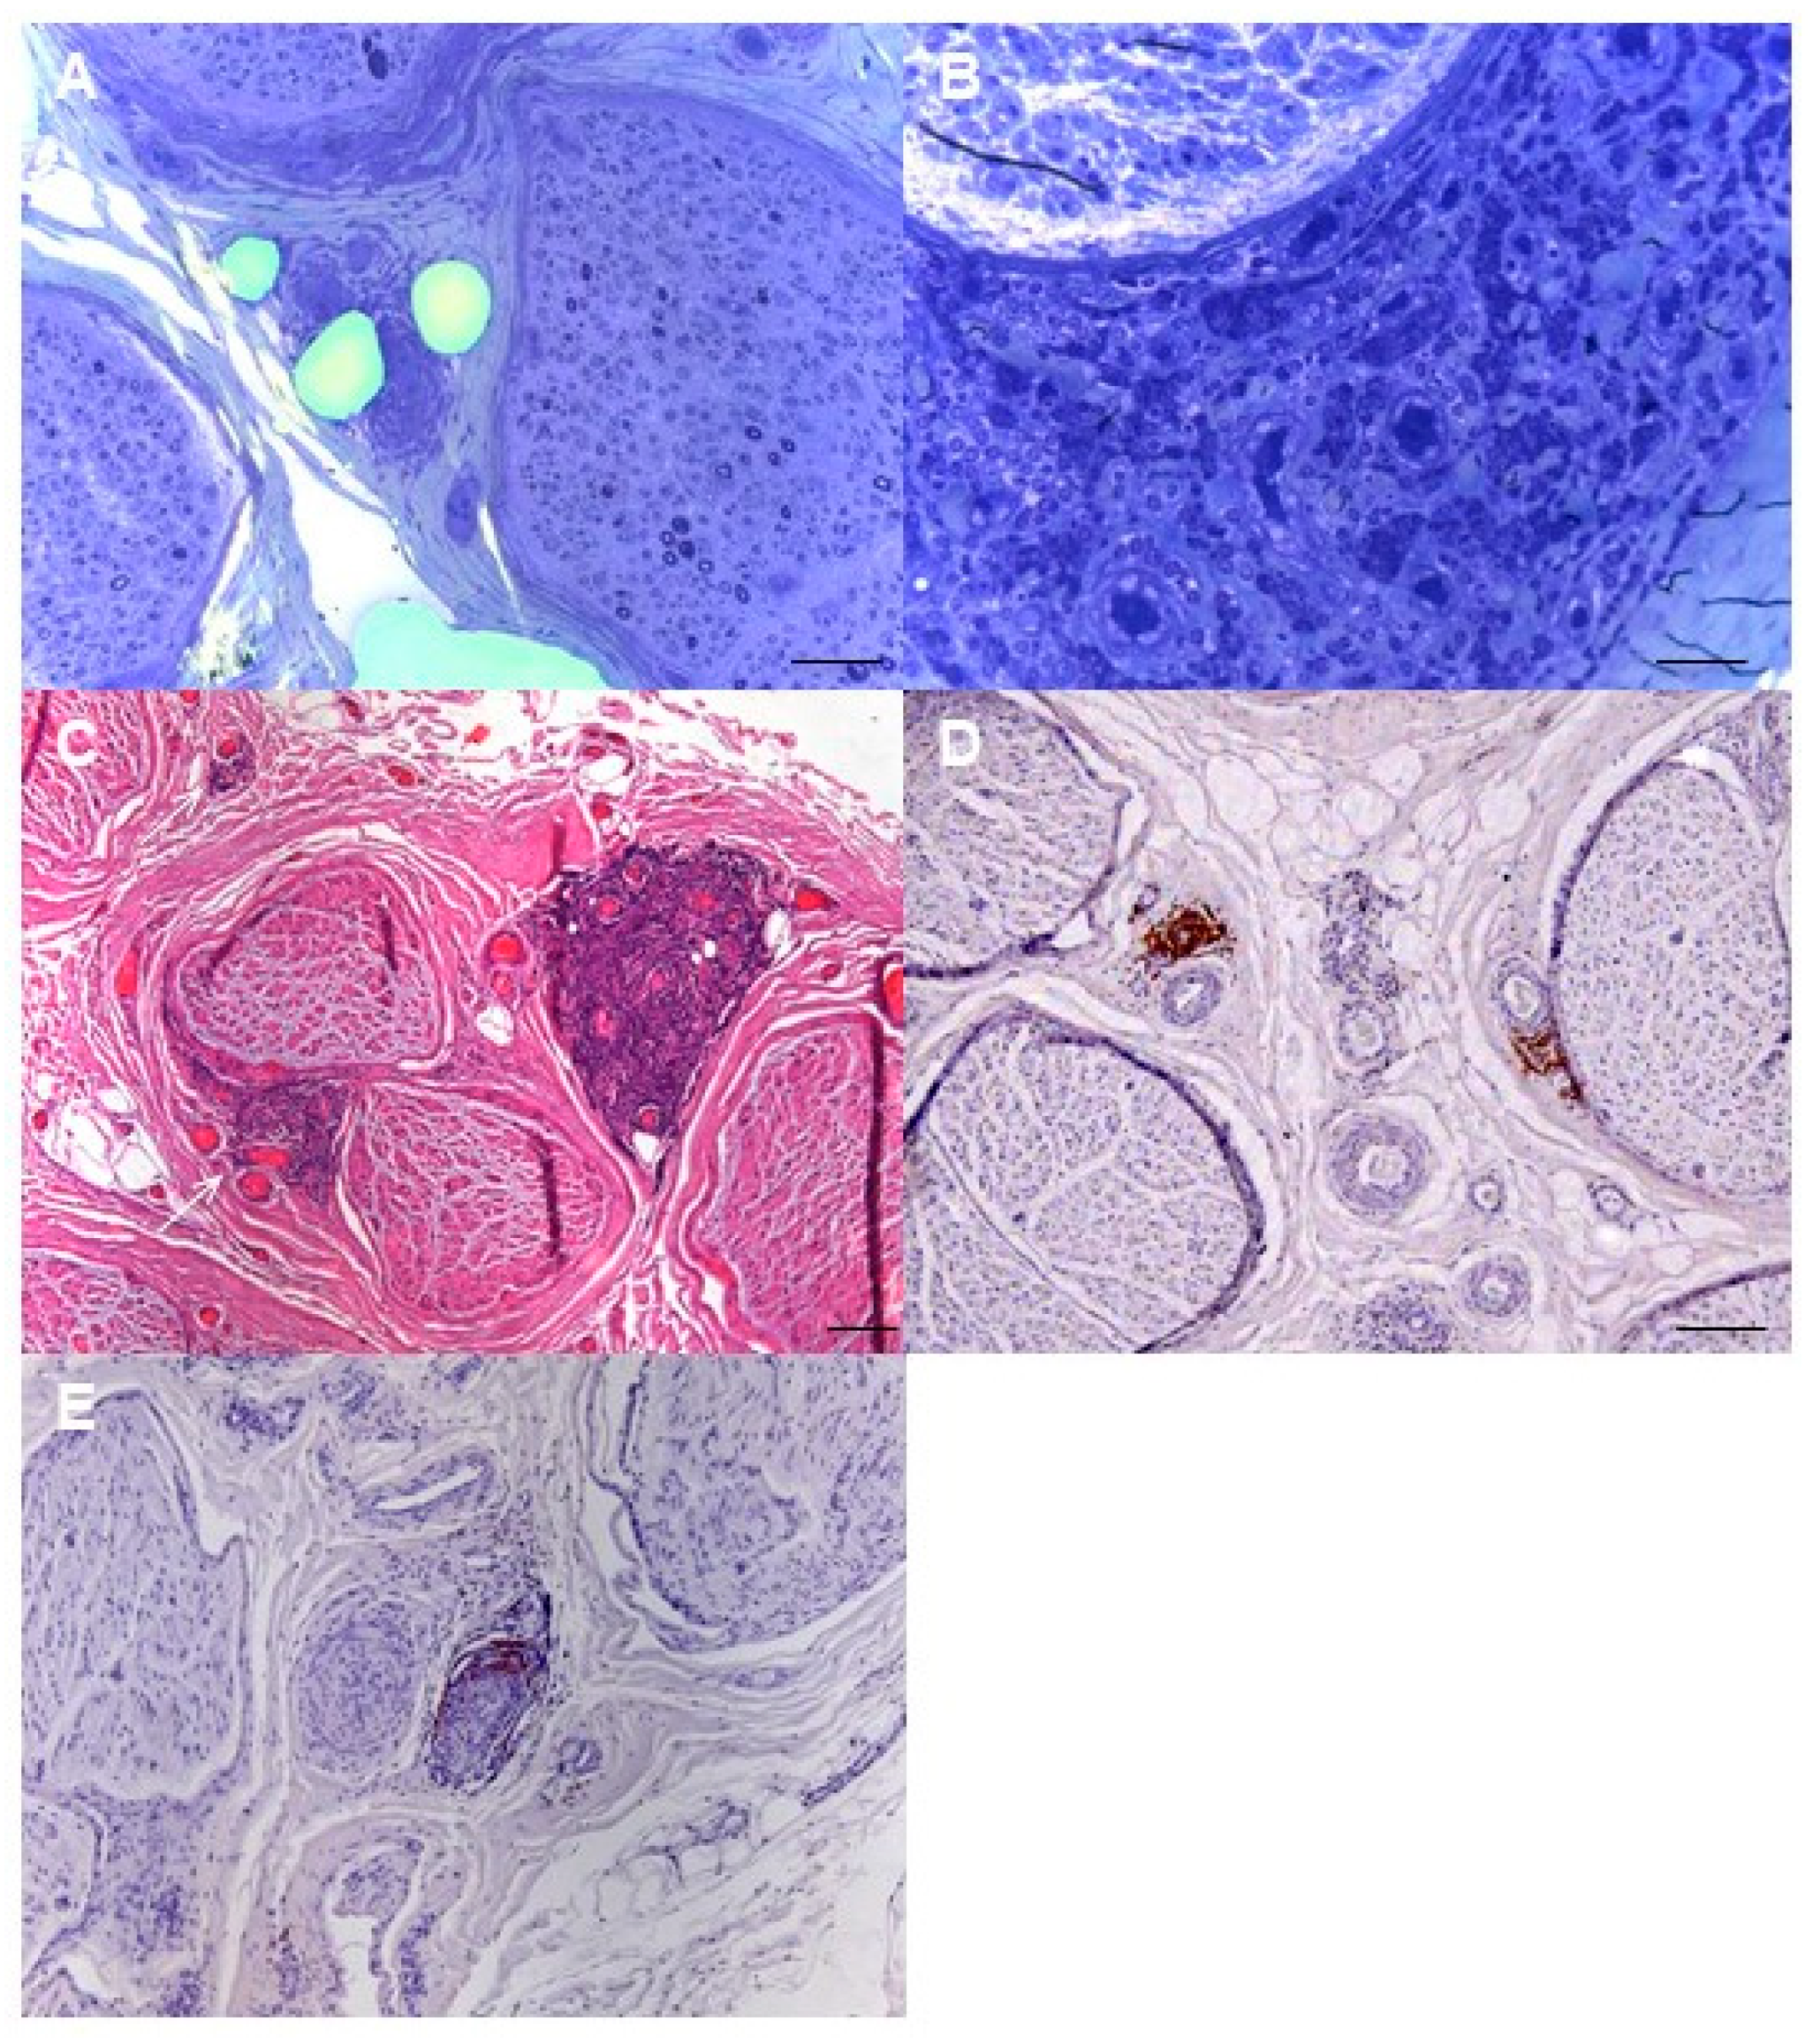

Mechanisms of Nerve Damage in Neuropathies Associated with